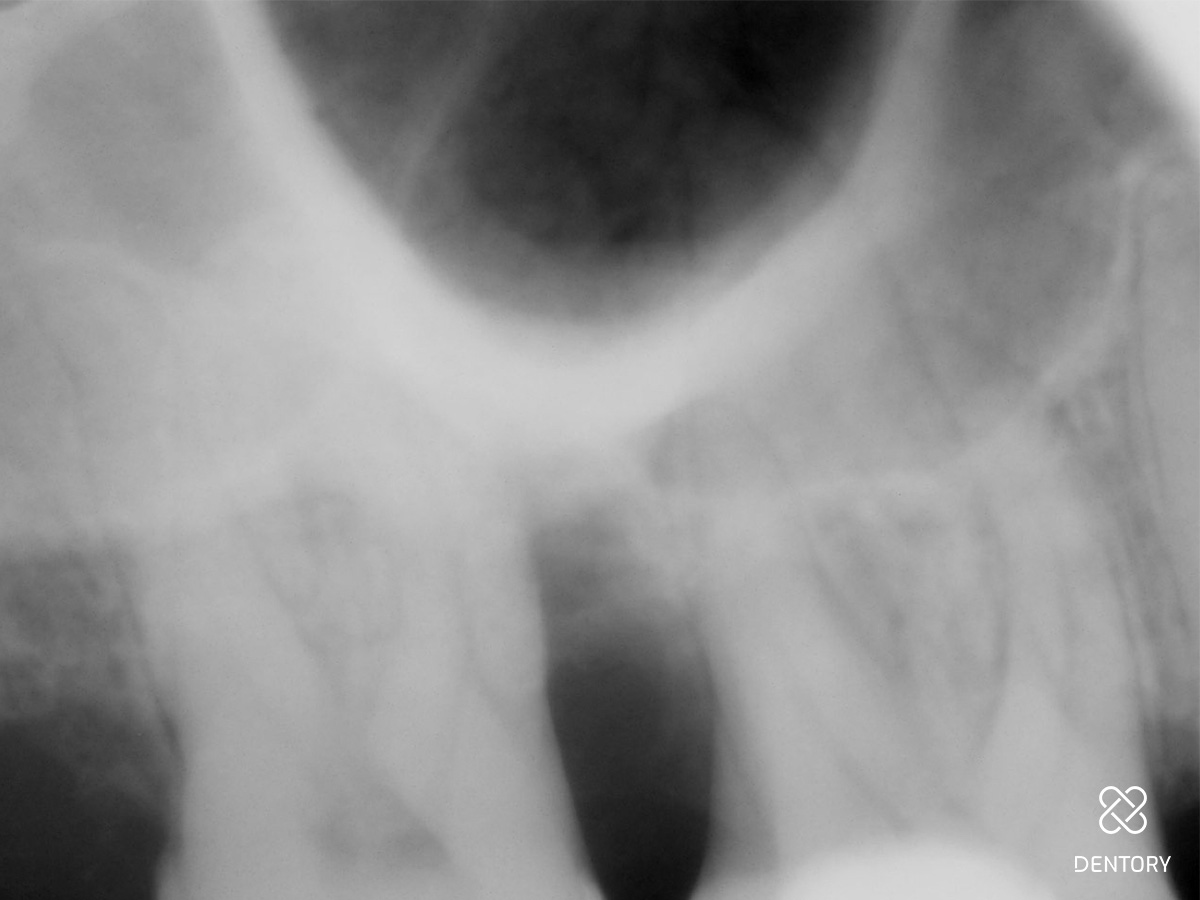

Abbildung 17

Das Röntgenbild von 17 weist mesial eine knöcherne Auffüllung des Defektes auf.